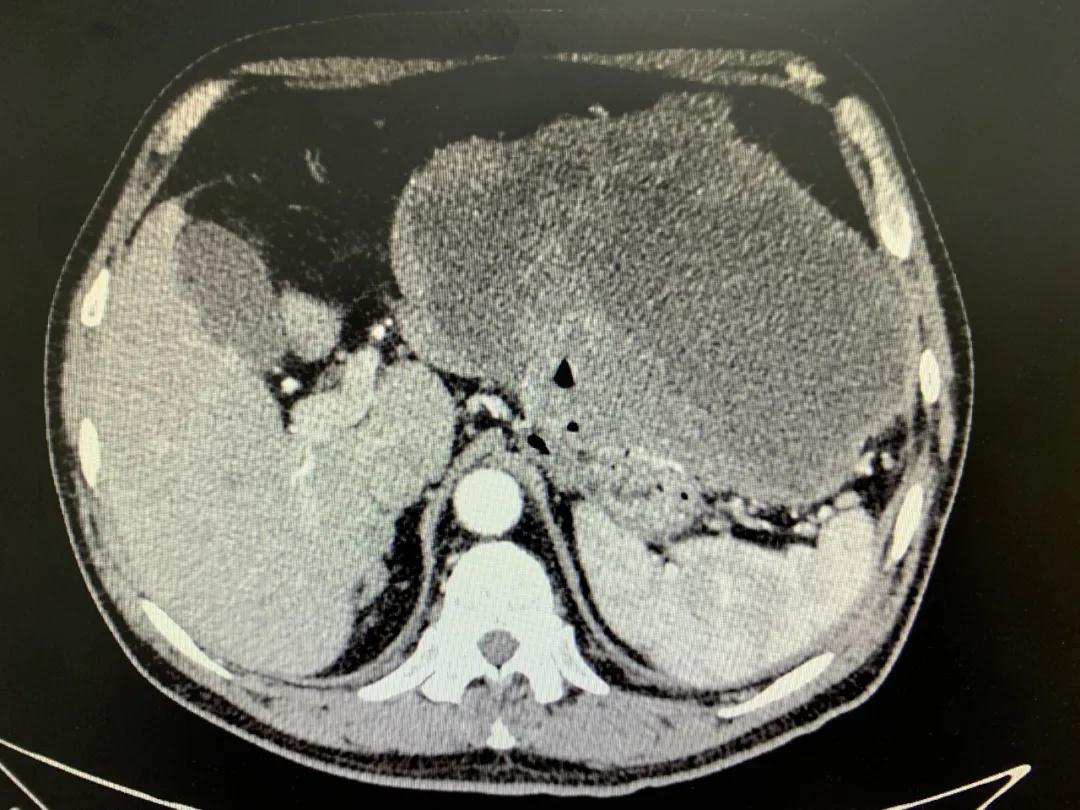

患者入院時(shí)血紅蛋白數(shù)值仍持續(xù)下降,出現(xiàn)失血性休克表現(xiàn),危及生命。消化外科二病區(qū)蔡磊主任接診后,組織科室迅速對(duì)患者進(jìn)行了全面的檢查。CT提示腫瘤大小約19.3*10.3cm,腫瘤內(nèi)提示大量積血。結(jié)合相關(guān)檢查,考慮為罕見(jiàn)的巨大胃間質(zhì)瘤合并出血。

蔡磊主任團(tuán)隊(duì)立即為患者安排了手術(shù),術(shù)中發(fā)現(xiàn)腫瘤巨大,占據(jù)大部分胃壁,胃腔內(nèi)殘存血液達(dá)3400ml之多,且多為新鮮活動(dòng)性出血,給手術(shù)增加了非常大的難度。但蔡磊主任團(tuán)隊(duì)克服困難,在麻醉手術(shù)中心的幫助下,終于將腫瘤完整切除,術(shù)后稱(chēng)量腫瘤達(dá)10斤重!